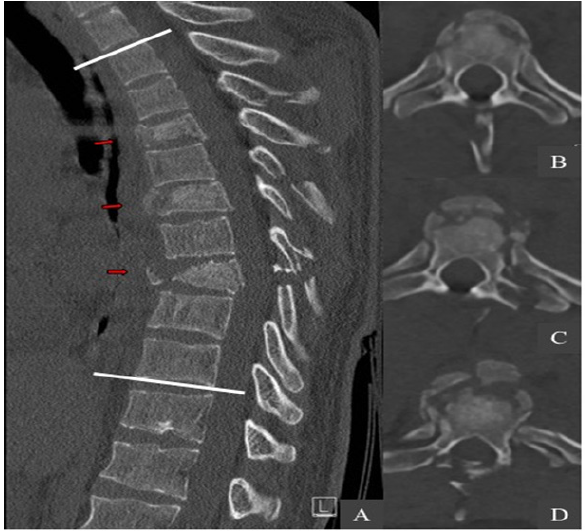

The initial whole-body computed tomography revealed three unstable noncontiguous vertebral body fractures distributed on Th4, Th6 and Th8. These were complicated by the association of multiple fractures of pedicles, spinous and transverse processes at adjacent thoracic spine levels (Figure1). These fractures were graded according to AO Spine classification as it follows: type A4 with 32% vertebral compression on Th4; type A3 with 18% vertebral compression on Th6; type B2 with 75% vertebral compression on Th8 (Table 1). The regional kyphosis between Th2 and Th10 was measured with an angle of 38.5°. The computed tomography also revealed a fracture of the sternal manubrium, multiple bilateral rib fractures from Th5 to Th9 and a left great trochanter fracture. Interestingly the whole spine MRI assessment did not show any spinal cord injury neither epidural lesions. The ISS was measured at 24.

Figure 1: Preoperative CT-scan. (A) The sagittal and axial views show three unstable noncontiguous vertebral body fractures (red arrows) distributed on Th4 (B), Th6 (C) and Th8 (D). The regional kyphosis was measured with an angle of 38.5° between Th2 and Th10 (white lines).